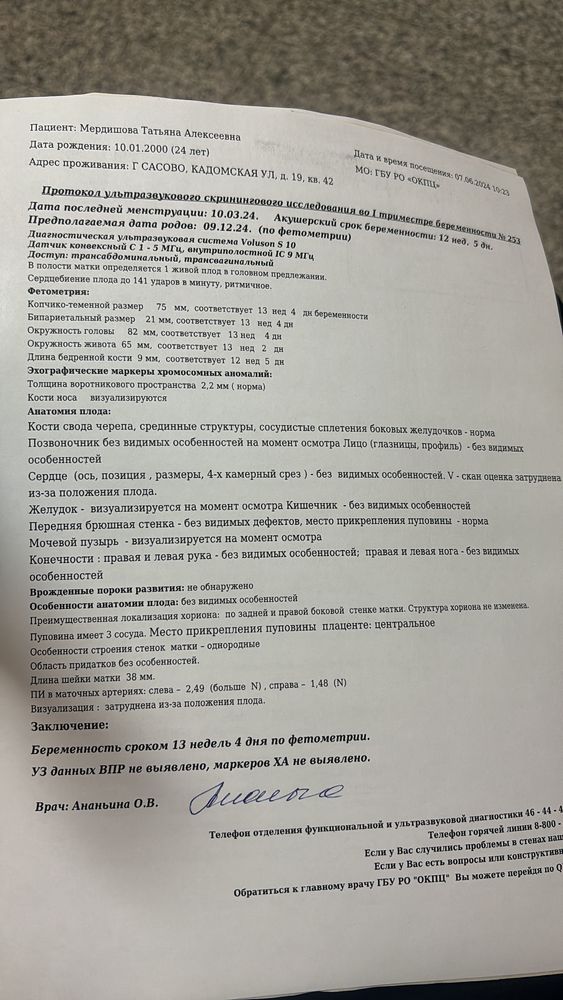

Подскажите пожалуйста кто на фоточке, предположение что мальчик, не могу точно понять

Вы и не поймете на этом сроке.Опытные узисты говорят с вероятностью 25%.